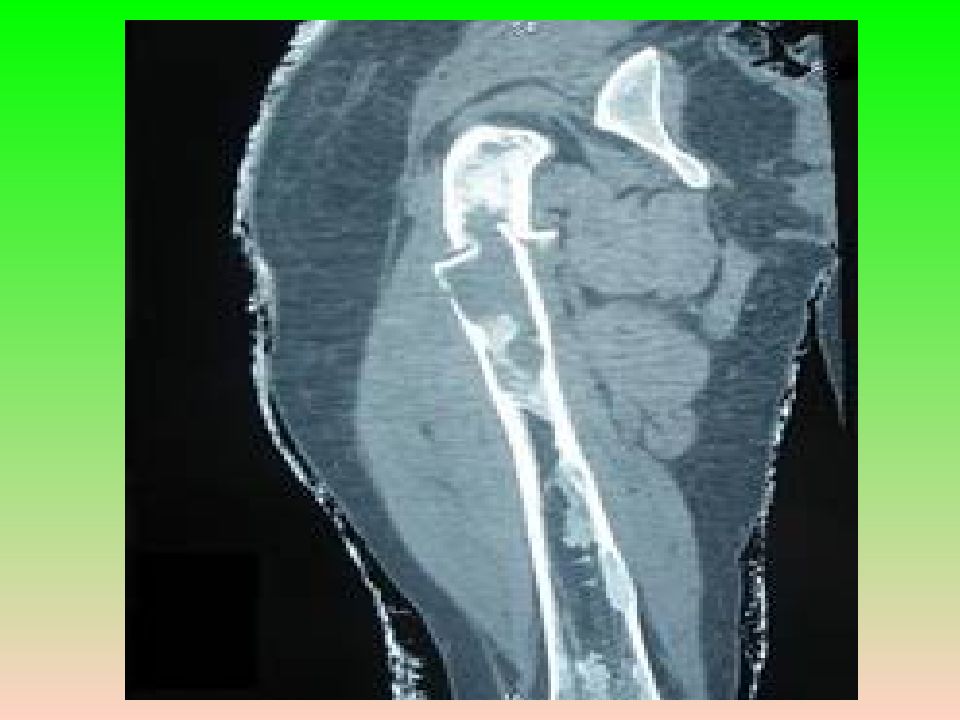

Боли различной интенсивности, искривление и деформация костей, патологические переломы.  Рентгенологически — литическое поражение с чёткими контурами и склерозированными краями; может быть вздутие кости, патологический перелом. Клиническая картина

Слайд 11: Патоморфология

Макроскопически — плотная ткань бело-серого цвета с мелкими включениями костной плотности. Патологическая ткань почти всегда располагается только внутри костномозгового канала. Патоморфология